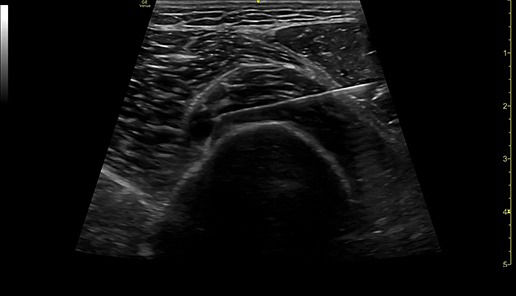

PRECISION NEEDLE GUIDANCE

Accurately guide and visualize injections

Even in the most experienced hands, blind injections—those performed without imaging—are not 100% accurate. By using ultrasound for needle guidance, the needle is highlighted and you have quality visualization of joints and soft tissue during procedures at a lower acquisition cost than other imaging modalities.

Excellent visualization with Needle Mode

Needle Mode also allows you to easily differentiate between the needle and patient anatomy with confidence—allowing you to quickly guide the needle exactly where it needs to be and helping to minimize patient discomfort.